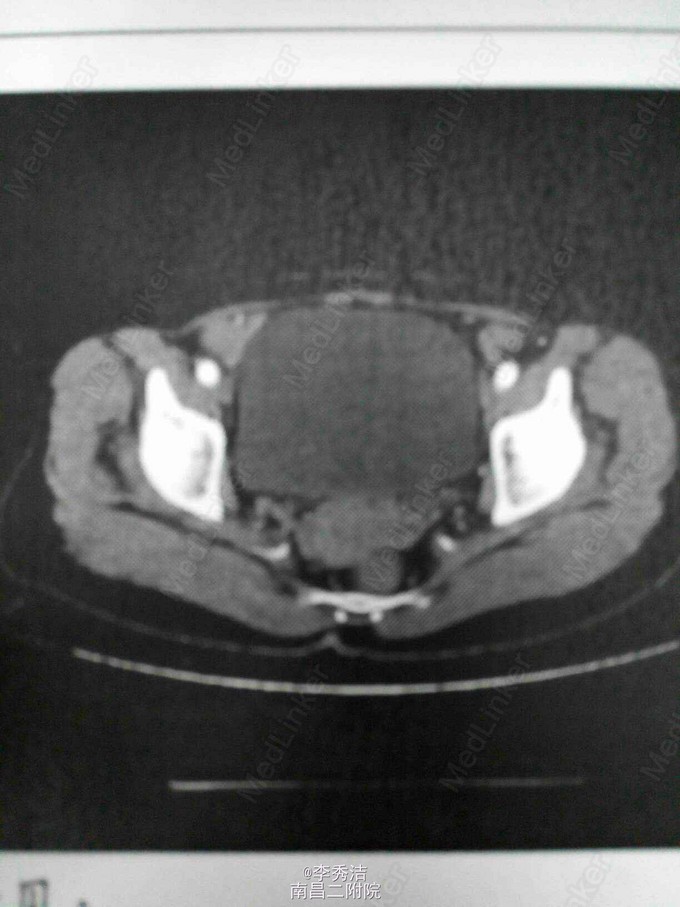

患者女,55岁,一周前体检发现宫颈癌,无任何自觉症状。诊断性刮宫病理结果示:子宫颈中分化浸润性磷状细胞癌。给予全子宫+双附件切除加盆腔淋巴结清扫,后期予顺铂+紫杉醇化疗。